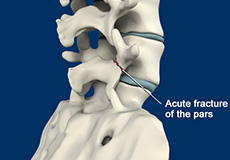

Spondylolysis

Spondylolysis is a stress fracture in the vertebra that may progress into spondylolisthesis, a condition where the vertebra gets displaced from the spinal column. Spondylolysis is the cause of frequent low back pain in children. It is more common among children and teenagers who participate actively in sports such as football, weightlifting, and gymnastics.